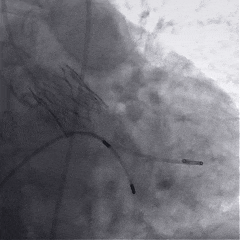

术中影像

根部造影

球囊预扩

瓣膜稳定释放

瓣膜展开后造影

再次造影,确认瓣膜位置

脱钩后造影,瓣膜位置可,几乎无瓣周漏